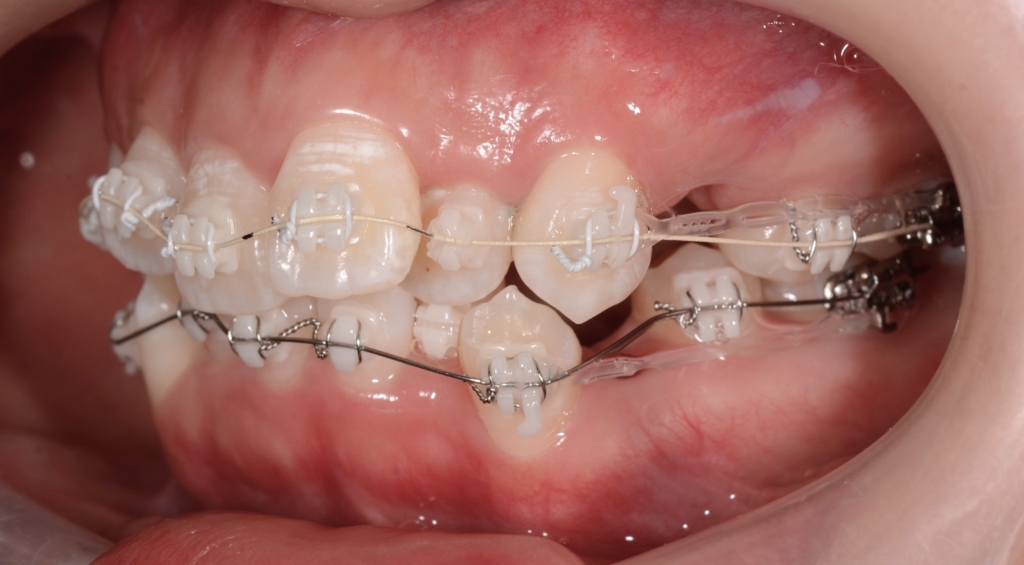

マルチブラケットシステム(ハーフホワイトtype)で矯正治療を開始。

前歯の乱れが解消され、きれいに並んだので、次のステップに入ります。

上下とも前歯を後方へ最大限に引っ込めて行きます

この方の写真が見つからないので、同じことをしている方の写真をイメージ写真としてあげています